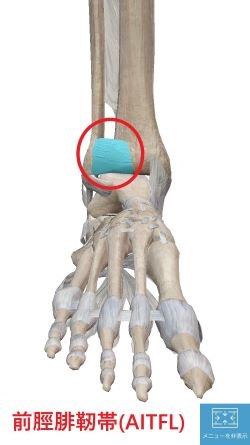

今回は足関節捻挫

④二分靭帯の損傷です。

場所は外くるぶしの前方

少し足の甲側へいった辺りです。